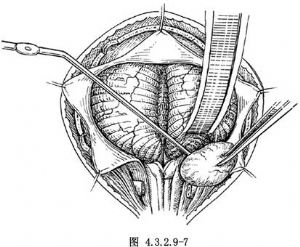

4.先遊離瘤體,並電凝切斷供血動脈,將第9、10、11顱神經剝開並加以保護。用電刀逐步將腫瘤基底自硬腦膜分離。並向後外牽引,達到將腫瘤完整切除(圖4.3.2.9-7)。較大的腫瘤可採取分塊切除。